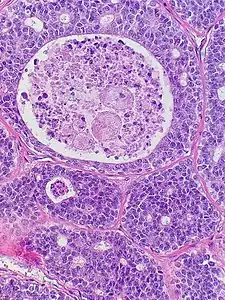

| Micrograph of an adenoid cystic carcinoma of a salivary gland (right of image): Normal serous glands, typical of the parotid gland, are also seen (left of image), H&E stain. | |

Histopathological image of adenoid cystic carcinoma of the salivary gland infiltrating a nerve (center), H&E stain

Adenoid cystic carcinoma with comedonecrosis